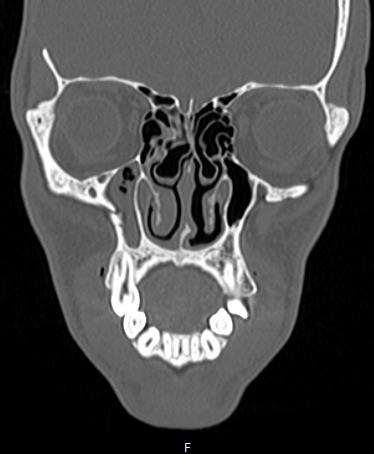

Лицевой череп состоит из крупных костей (верхняя и нижняя челюсти, лобные кости, скуловые кости) и сгруппированных вокруг них остальных мелких костей. При травмах лицевых костей часто наблюдается смещение мелких отломков, которые не видны при обычной рентгенографии. Мультиспиральная компьютерная томография позволяет детально изучить кости лицевого черепа, а также углубления, которые являются вместилищем для важных органов (глазницы, полость носа, ротовая полость).

Метод КТ основан на применении рентгеновского излучения и различной способности тканей поглощать рентгеновские лучи. Костные структуры обладают наибольшей плотностью по сравнению с другими тканями, поэтому в большей степени поглощают рентгеновские лучи и лучше всего визуализируются при данном исследовании.

КТ костей лица является наиболее информативным методом диагностики травм лицевого черепа, посттравматических деформаций, аномалий развития, инородных предметов в носовой полости и околоносовых пазухах. Кроме того, мультиспиральная КТ применяется при воспалительных заболеваниях ЛОР-органов, а также для выявления опухолевых образований доброкачественного и злокачественного характера.

Детальные изображения костей лицевого черепа получаются за счет вращения трубки томографа с излучателями рентгеновских лучей вокруг объекта исследования. В аппаратах увеличено количество сверхчувствительных детекторов, позволяющих производить множество послойных снимков с толщиной среза от 0,5 мм, которые затем преобразуются в трехмерные пространственные модели черепа. Такие инновационные возможности аппаратов обеспечивают проведение точной и достоверной диагностики.